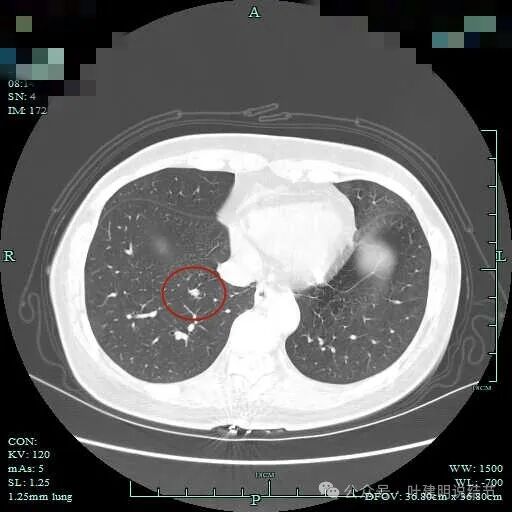

病灶B整体都变实性了,轮廓与边界清。

局部放大看,病灶B基本上都变成了实性,而且密度较高,有见到微小血管走向病灶。